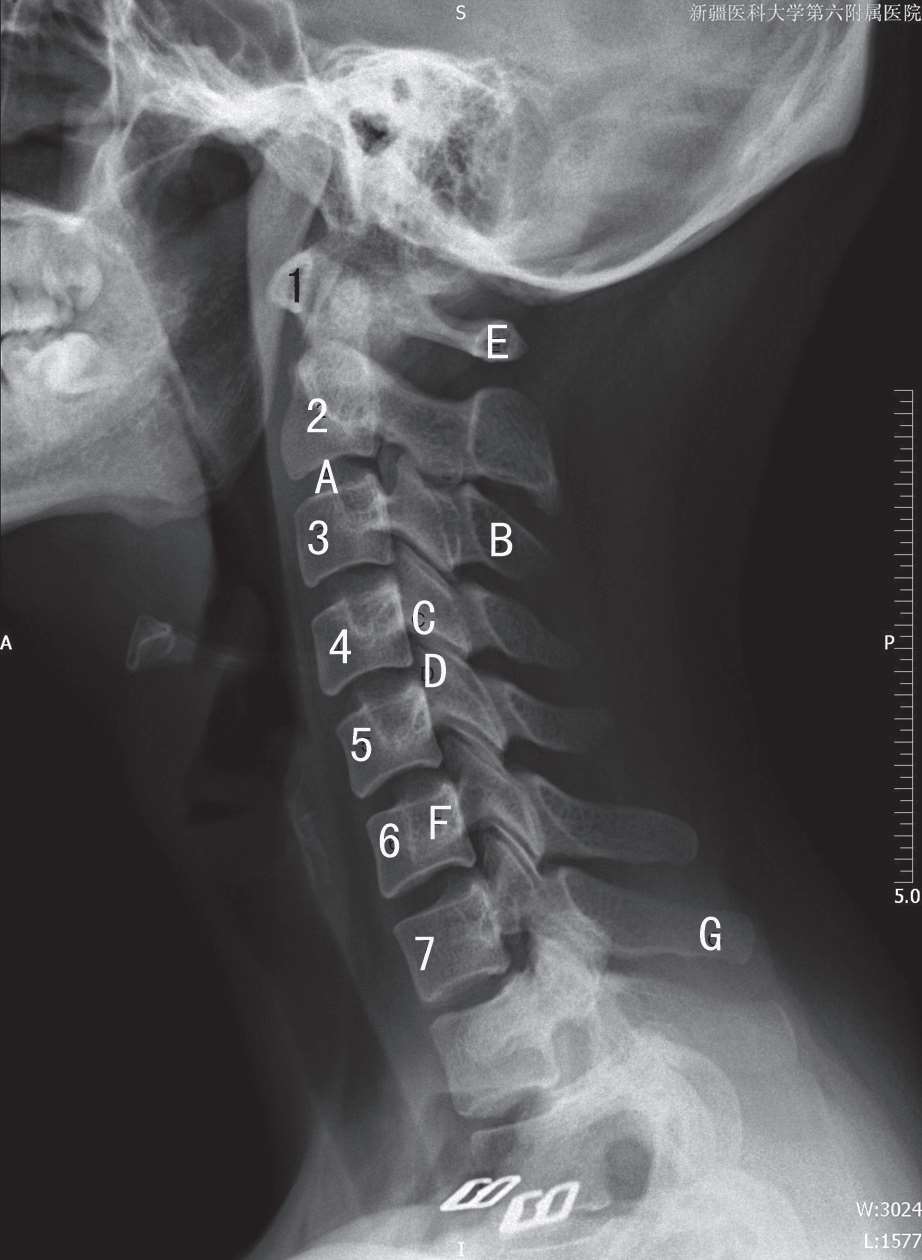

患者取仰卧位或侧向坐于摄影架前。下颌上仰使听鼻线与躯体冠状面垂直,避免下颌支与上部颈椎重叠,为了不影响颈部的生理曲度,绝不要勉强患者做出该姿势。双肩尽量下垂,避免肩部与C 6 、C 7 重叠,身体正中矢状面与片盒平行,胶片上缘包括外耳孔,下缘抵颈静脉切迹。中心线与胶片垂直,经甲状软骨处颈部前后缘中点射入(图3-5)。若定位的重点为上部颈椎或下部颈椎,可适当上移或下移。曝光时患者需深吸气后屏气。该投照位置显示C 1 ~C 7 颈椎侧位影像,能观察颈椎的生理曲度上部包括部分枕骨和下颌骨,前部包括喉部软组织及其前后方其他软组织。椎体的形态、椎间隙、棘突、椎间关节、椎管前后径显示清晰(图3-6)。

1. 寰椎前弓;A. 椎间隙;B. 棘突;C. 下关节突;D. 上关节突;E. 寰椎后弓;F. 横突;G. 隆椎(C 7 棘突)(C 2 ~C 7 颈椎体上标有数字)

图3-6 颈椎侧位片